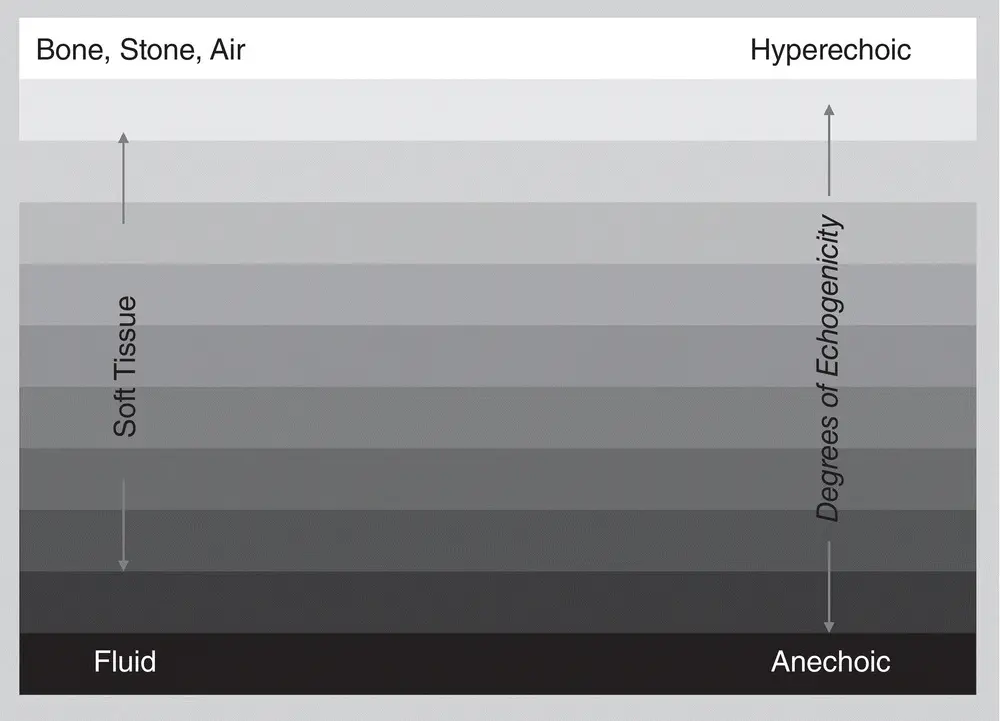

Echogenicity – Whites, Grays, and Blacks

The jargon of ultrasound can be intimidating to the novice sonographer. Clarity may be accomplished through acknowledging that ultrasound is generally the opposite of how free fluid, air, and soft tissue appear on radiographic studies (our brain needs to reformat itself). For example and very simplistically, air is white on ultrasound and black on radiographs. Fluid is black on ultrasound and white on radiographs. However, bone is black (shadows) on ultrasound? And white on radiographs? Or white along its proximal surface with acoustic shadowing through the far field. Now if we are losing you, hang in there. The figures help ( Figures 1.2, 1.3, 1.4, 1.5). Study them now .

The ultrasound terms describing whites, grays, and blacks are anechoic (black), degrees of echogenicity (hypoechoic, shades of gray), and hyperechoic (white). The terms may be used relatively between structures like “X relative to Y” and “Y relative to Z.” For example, the spleen is hyper echoic (brighter than) to the left kidney. The liver is hypo echoic (darker than) to the falciform fat. The feline cortex of the kidney is isoechoic (same as) to the spleen (see Figure 1.3).

Figure 1.2. The figure shows the ultrasound differences in B‐mode gray scale of various tissues, with bone, stone and air being most reflective of the ultrasound beam and thus portrayed as white along its surface, to soft tissues being shades of gray, to fluid which is black. Ultrasound terminology corresponds to these gray‐scale colors as hyperechoic, degrees of echogenicity (hypoechoic), and anechoic. Study this chart to get the visual of what these gray‐scale terms mean. Courtesy of Dr Gregory Lisciandro, Hill Country Veterinary Specialists and FASTVet.com, Spicewood, TX.

Figure 1.3. This figure is similar to Figure 1.2but with some of the gray scale removed to illustrate how descriptive ultrasound terminology is used for different tissues. The soft tissue is isoechoic (same as), hyperechoic (brighter than), and hypoechoic (darker than) relative to one another. Correlate with Table 1.1Courtesy of Dr Gregory Lisciandro, Hill Country Veterinary Specialists and FASTVet.com, Spicewood, TX.